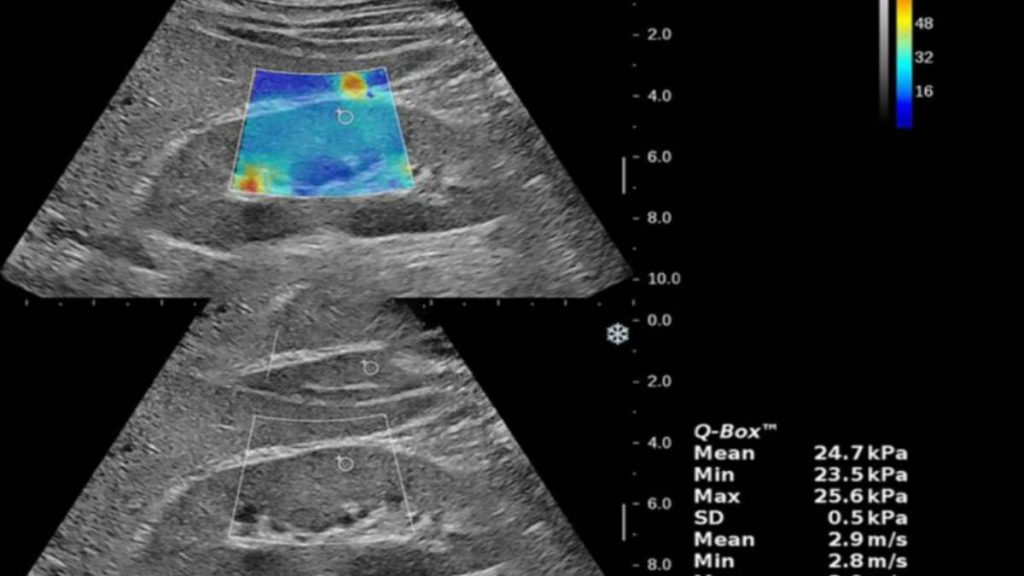

نتیجه فیبرو اسکن کبد معمولاً به شکل عددی گزارش میشود که نشاندهنده میزان سفتی کبد است. این عدد به واحد kPa (کلیو پاسکال) اندازهگیری میشود و هر چه این عدد بالاتر باشد، نشاندهنده فیبروز شدیدتر و احتمال آسیب بیشتر به بافت کبد است. پاسخهای فیبرو اسکن در مقیاسهای مختلف تفسیر میشوند که شامل فیبروز مرحله صفر (بدون فیبروز) تا فیبروز مرحله چهار (سیروز کامل) میشود.

در تفسیر جواب، ابتدا مقدار عددی SFT (سفتی کبد) بررسی میشود. معمولاً برای تشخیص میزان فیبروز، مقدار SFT زیر ۷ کپا نشاندهنده کبد سالم است و بیشتر از ۱۲ کپا به احتمال زیاد به سیروز کبدی اشاره دارد. در موارد بین این دو عدد، پزشک باید به موارد بالینی و آزمایشات دیگر نیز توجه کند.

معیارهای تفسیر فیبرو اسکن

- زیر ۶ kPa: کبد سالم، بدون فیبروز

- ۶–۸ kPa: فیبروز خفیف (مرحله 1-2)

- ۸–۱۰ kPa: فیبروز متوسط (مرحله 2-3)

- ۱۰–۱۲ kPa: فیبروز شدید (مرحله 3)

- بالای ۱۲ kPa: سیروز کبدی (مرحله 4)